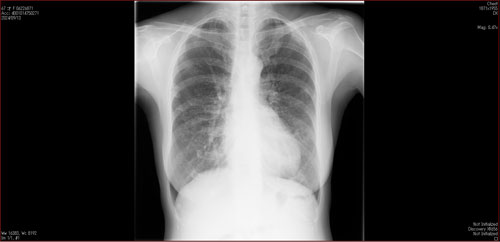

肺X線画像

- 2023.05.11 要観察と診断された画像(国立系病院)